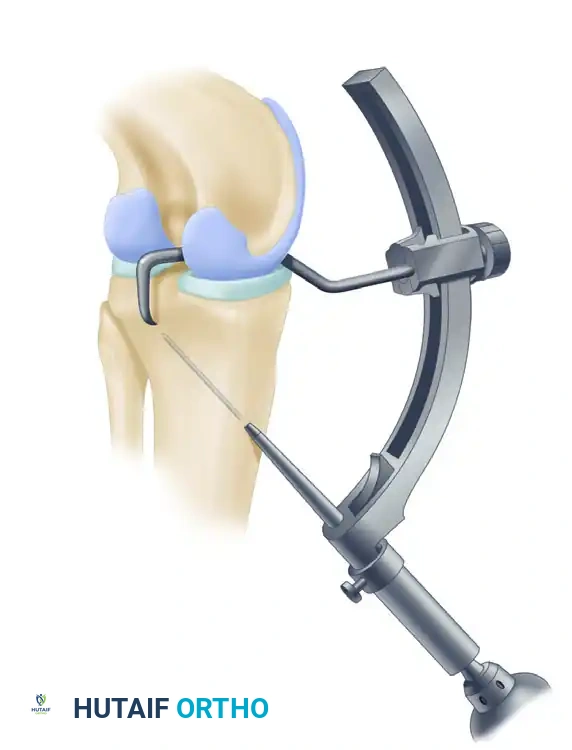

- Guide Placement: We recommend the Arthrex drill guide system. With the 70-degree arthroscope in the AL portal, insert the tibial guide through the AM portal and pass it through the intercondylar notch.

- Targeting the Footprint: Place the tip of the guide 10 to 12 mm below the joint line, directly in the center of the native PCL facet on the posterior tibia.

- Setting the Angle: Orient the drill guide at approximately 60 degrees relative to the articular surface of the tibia. The starting point should be just inferior and medial to the tibial tuberosity.

Arthrex Popliteal Drill Stop prevents advancement of the guide pin past the tip of the marking hook during drilling, ensuring neurovascular safety.

- Fluoroscopic Confirmation: The simultaneous use of lateral image intensification (fluoroscopy) and arthroscopy is mandatory to confirm the proper positioning of the drill guide before and during drilling.

- Pin Advancement: Calibrations on the tibial guide accurately measure the distance from the anterior tibial cortex to the posterior tip of the guide. Adjust the guide pin so that it protrudes from the drill exactly 1 cm less than the measured distance. This mechanical stop prevents catastrophic overdrilling.

- Tapping the Pin: Drill the pin until it reaches the 1 cm stop. Then, disconnect the drill and tap the pin in the final 1 cm with a mallet.

- Neurovascular Protection: While tapping the pin, place a curette through the PM portal over the posterior tibial cortex. This acts as a physical barrier to protect the neurovascular structures from inadvertent pin penetration. If adequate capsular elevation was performed, the guide pin will be clearly observed arthroscopically as it exits the posterior tibia at the physeal scar area.

- Reaming: Ream the tibial tunnel over the guide pin to the matched diameter of the graft (usually 10 or 11 mm).